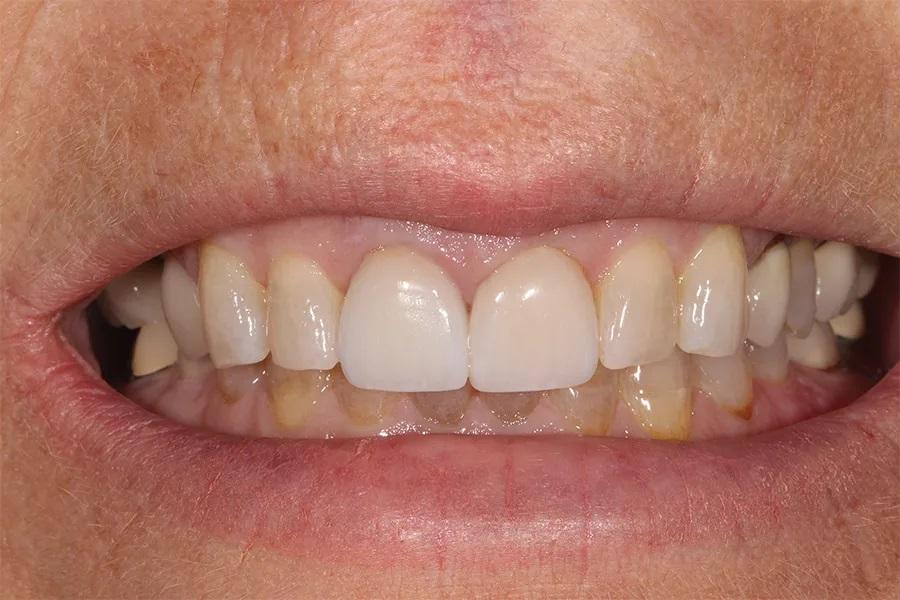

Пациентка, 58 лет, стоматолог-гигиенист, обратилась с жалобами на повторяющиеся неудачи реставрационного лечения. Она испытывала неудовлетворенность своим внешним видом (фото 1–3) и хотела получить более гармоничную, симметричную улыбку с более светлым оттенком зубов и меньшей выраженностью десневой улыбки. Будучи специалистом в области стоматологии, она понимала ограничения лечения отдельных зубов и, после многих лет разочарования, обратилась за комплексным долгосрочным решением, способным обеспечить стабильность, улучшить эстетику и предотвратить дальнейшее разрушение.

Фото 2. Крупный план улыбки до лечения, демонстрирующий несоответствие реставраций в различных участках зубного ряда.